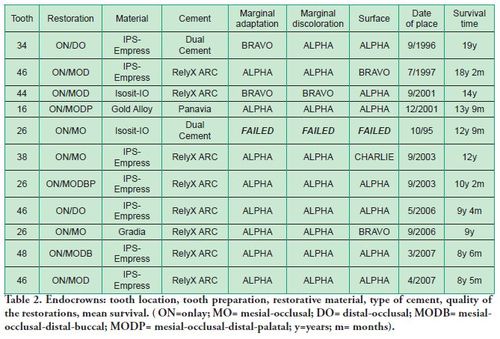

Three restorative materials and three resin cements were used (Table 2).

At the time of the examination, 10 (90.9%) ECs were in function in 10 patients. One EC had been lost after 12 years and 9 months due to periodontal disease in tooth #26. No restoration had loosened. Neither secondary caries nor radiographic failures were observed in the 10 PETT in function (Figs. 1a,1d; 2c; 3c,3d; 4c).

Three ECs in function were placed in maxillary molars, 5 in mandibular molars and 2 in mandibular premolars, yielding a ratio of 4.0 molars/premolars (Table 2).

Two small “chippings” in occlusal surfaces were polished. However, the Success Criteria on the quality of the restorations was rated as follows: Excellent 5 (50%), Good 4 (40%) and Functional Survival 1 (10%) (Table 2).